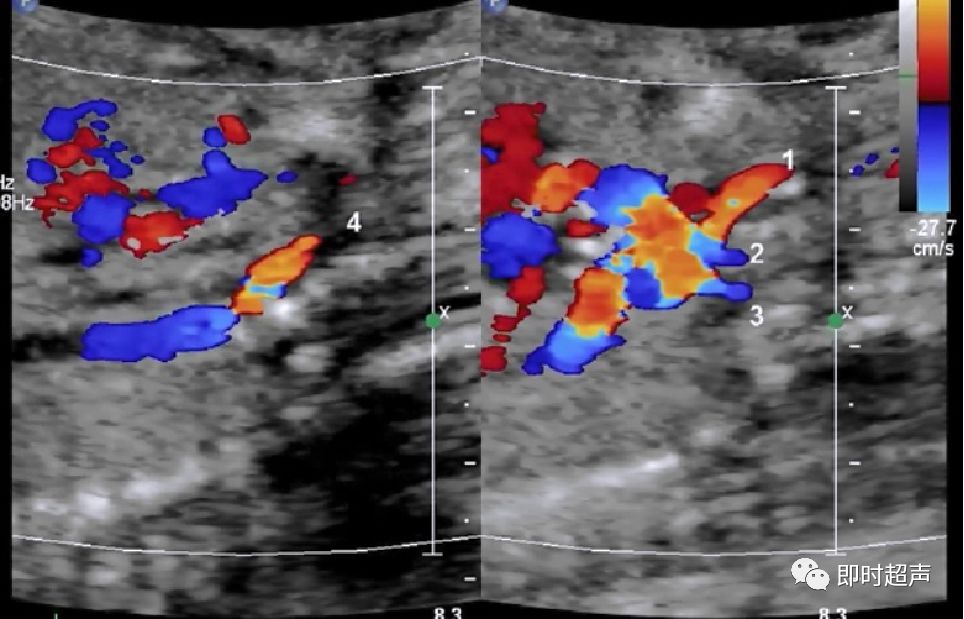

肺动脉增粗、主动脉正常

肺动脉瓣缺如症